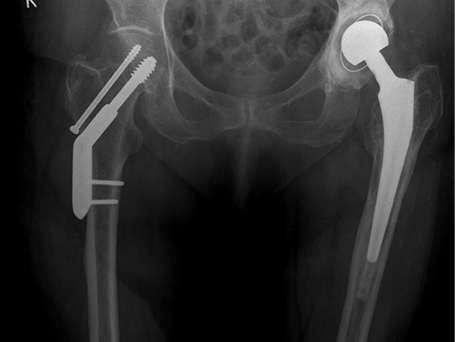

Über 80-jährige Patientin mit kaum verschobener Schenkelhalsfraktur rechts wurde unmittelbar nach Unfall und Einlieferung mit einer hüftkopferhaltenden Osteosynthese (Dynamische Hüftschraube) versorgt. Die Speichenköpfchentrümmerfraktur wurde mit einem künstlichen Speichenköpfchen behandelt. Es wurde hier eine zementierte Variante gewählt. Zweieinhalb Wochen nach Sturz ist die Patientin selbständig am Gehstock noch in der Abteilung für Geriatrie mobilisiert und setzt Ihren Ellenbogen bei guter Beweglichkeit bereits in den alltäglichen Verrichtungen ein.